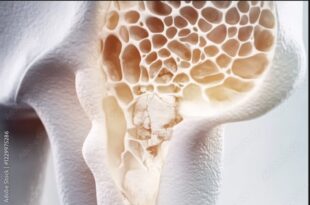

Read More »कौन सी हड्डियां कमजोर करती हैं ऑस्टियोपोरोसिस? 3 प्रमुख हिस्सों की पहचान करें